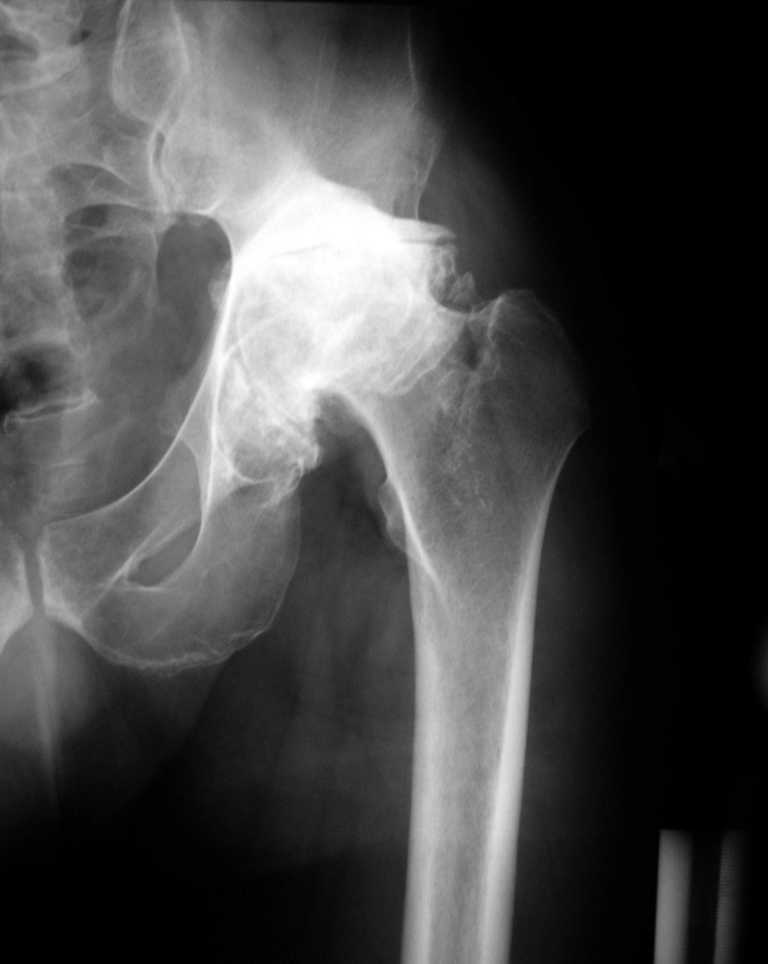

К нам обратился житель Казахстана с застарелым вывихом бедра. Травма год назад, вместо синтеза заднего края казахскими умельцами установлена клинковая пластина, через 6 мес удалена. Больной ходит с тростью,сгибание в т-б 90, разгибание 170, укорочение 5 см, боли не выражены, анальгетиками не пользуется. Настроен на эндопротезирование в клинике, где есть опыт подобных операций (возможно за рубежом).Наш план: аппарат таз-бедро, постепенное низведение бедра, "октопус" с пластикой. Но с такими большими дефектами мы не сталкивались.Есть вариант сначала аппарат, затем реконструкция впадины, протез обычный через 4-6 мес.Есть мнение не восстанавливать длину. Будем признательны за полезные советы. Было бы интересно посмотреть пример.

К сожалению, нередкая ситуация, мы предпочитаем выполнять операцию одномоментно - пластика задне-верхнего дефекта крыши ВВ собственной

головкой, установка вертлужного компонента бесцементной фиксации с обязательной дополнительной фиксацией винтами. Проблема будет в

восстановлении длины ноги, опыт показывает, что более 3-х см одномоментно восстановить очень сложно, и даже для этого потребуется широкая мобилизация бедра. В одном из номеров ж-ла Ортопедия травматология России мы опубликовали наш подход и р-ты лечения у больных с последствиями перелома ВВ.

Прилагаю в качестве иллюстрации одну из последних операций.

Еще одно наблюдение, неправильно сросшийся перелом заднего отдела ВВ с ввихом головки бедра 16-и летней давности.